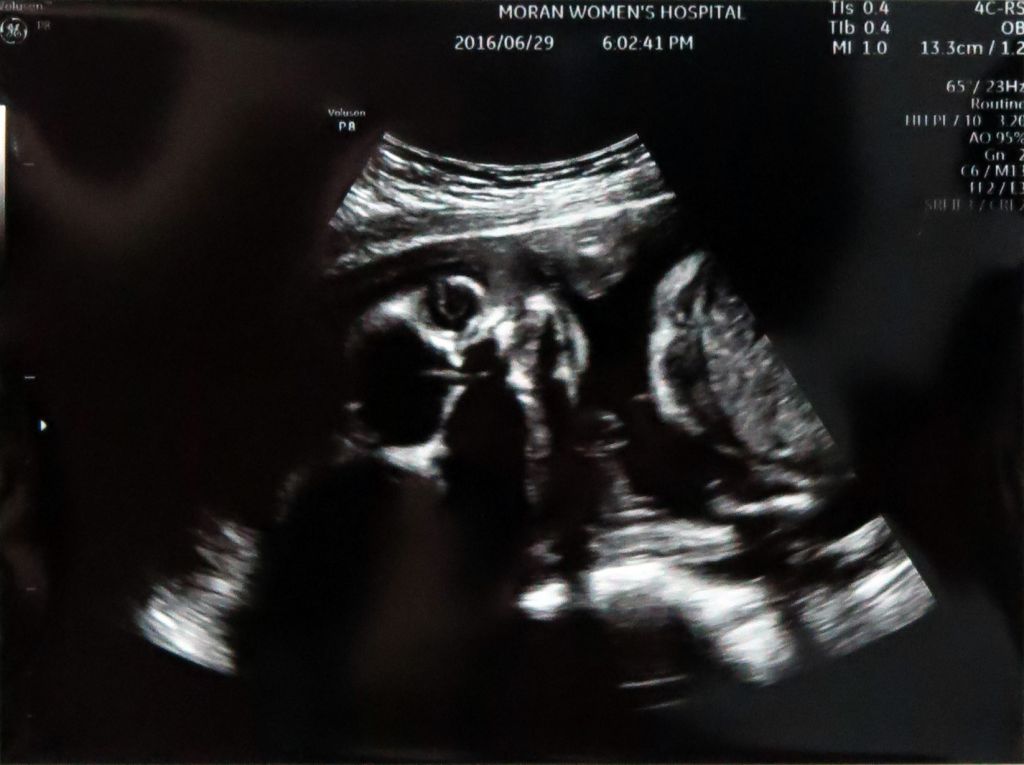

2016_06_29_2

하지만 얼굴은 너무 하셨네요;; 예쁘게 찍어주시지ㅠ